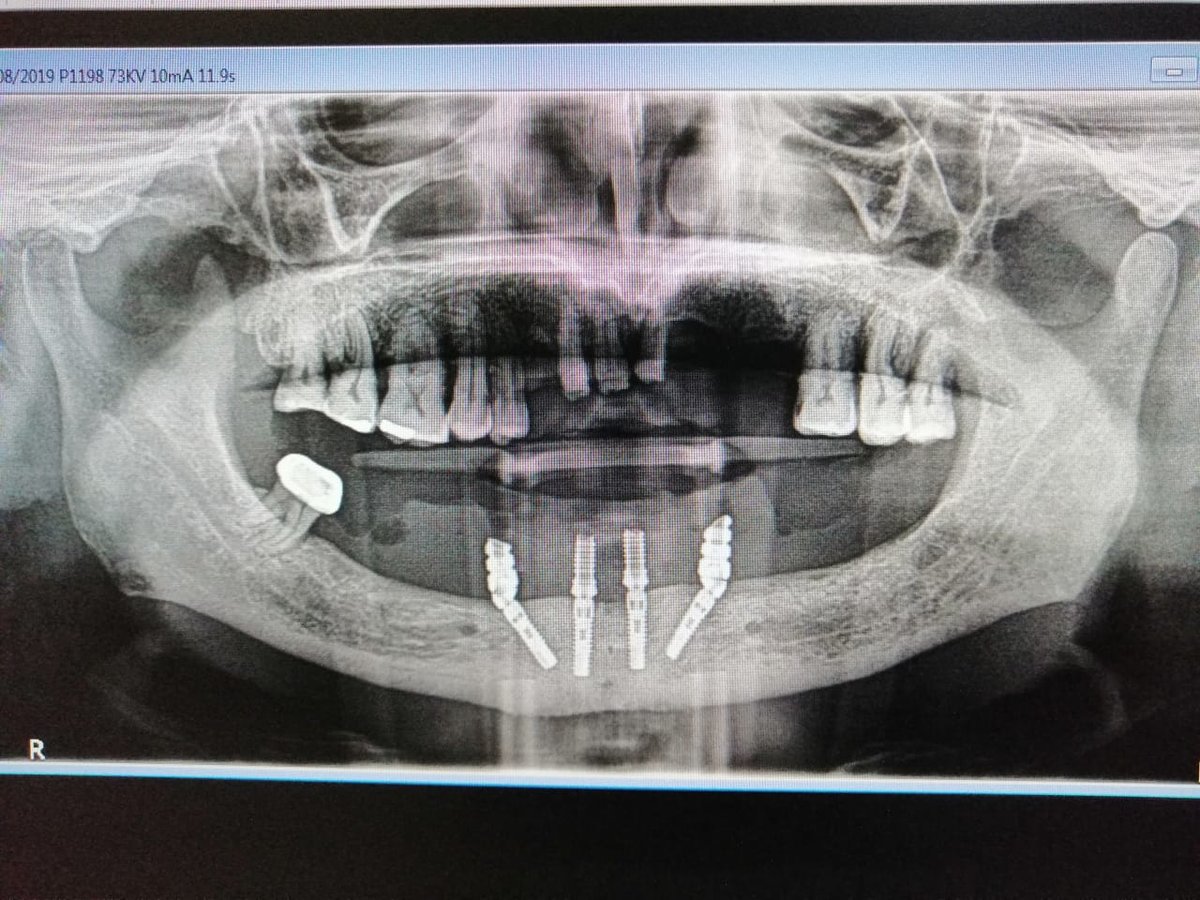

About Live Implants Nicaragua Virgil Mongalo DMD is a dental implant surgeon, past professor of implant surgeries at the University of Miami and the University of Florida has opened a surgical implant center in Managua. This is a state of the art facility consisting of equipped with Ct-scan, 3D Printer, zirconia milling machine, 8 surgical rooms, and USA sterilization controls. His team consists of implant surgeries professor accredited... (Show more)

| Dental Implants | $550 |

| Bone Graft | $300 |